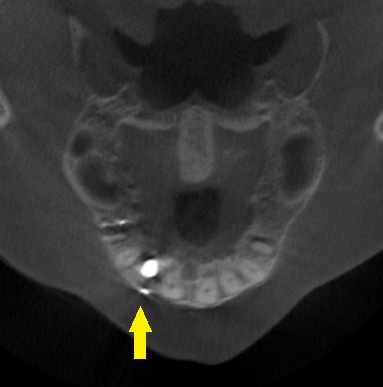

そこでインプラント埋入と同時に、口唇側に人工骨を補填して、骨の厚みを増やす骨造成術を併用することで、インプラント治療が可能であると提案させていただきました。

この手術方法で、同意が得られましたので、本日、インプラント埋入と同時骨造成術を行いました。

下の写真が、手術前後のCTです。